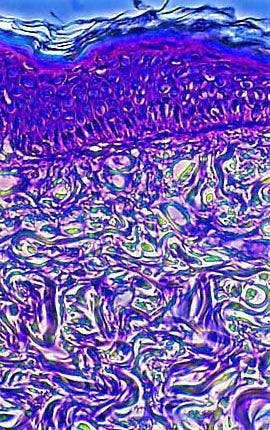

A stained thin section of human elpithelial tissue exhibiting damage from squamous cell papilloma virus is illustrated above. As evidenced by the micrograph, combining phase contrast microscopy with classical histological staining techniques in pathological research often yields enhancement of cellular features.